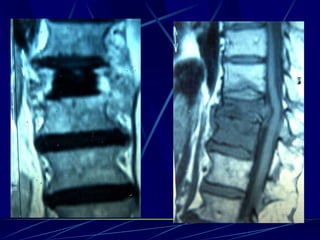

Infections of the spine

Epidural abscess

(Staphylococcus)

Φυματίωση της σπονδυλικής στήλης